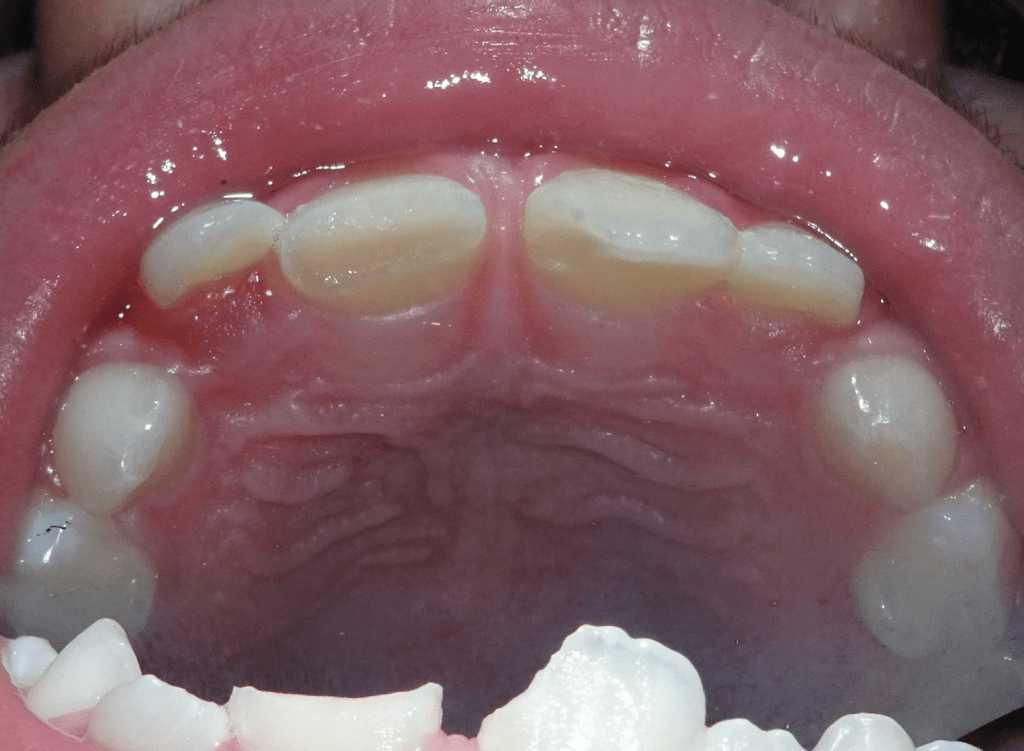

Reco palatina